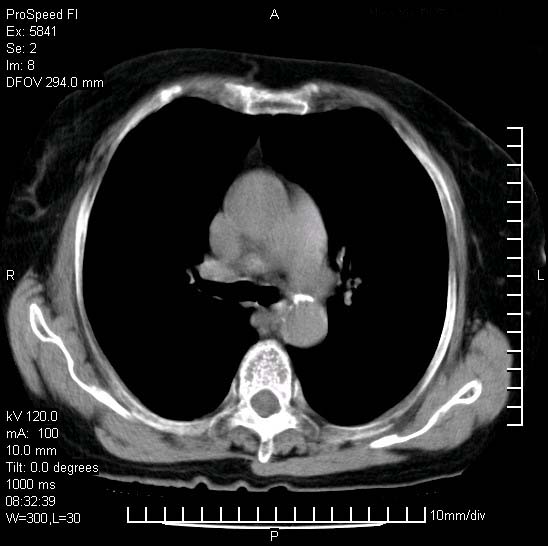

胸痛,咳嗽,气短一周,无发热。右上肺见一结节灶,边缘刺角,内见多个小钙化结节。考虑结核球?肿瘤? 余无异常没有上传。

考虑右肺上叶继发性肺结核,结核球形成。

慢性炎性病变,结核可能性大些。